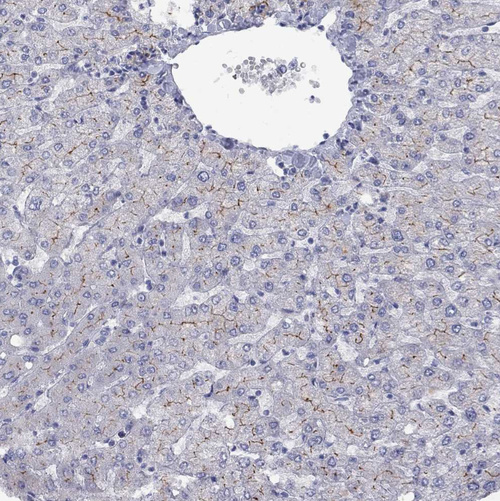

Immunohistochemical staining of human liver shows weak to moderate membranous positivity in bile duct cells.